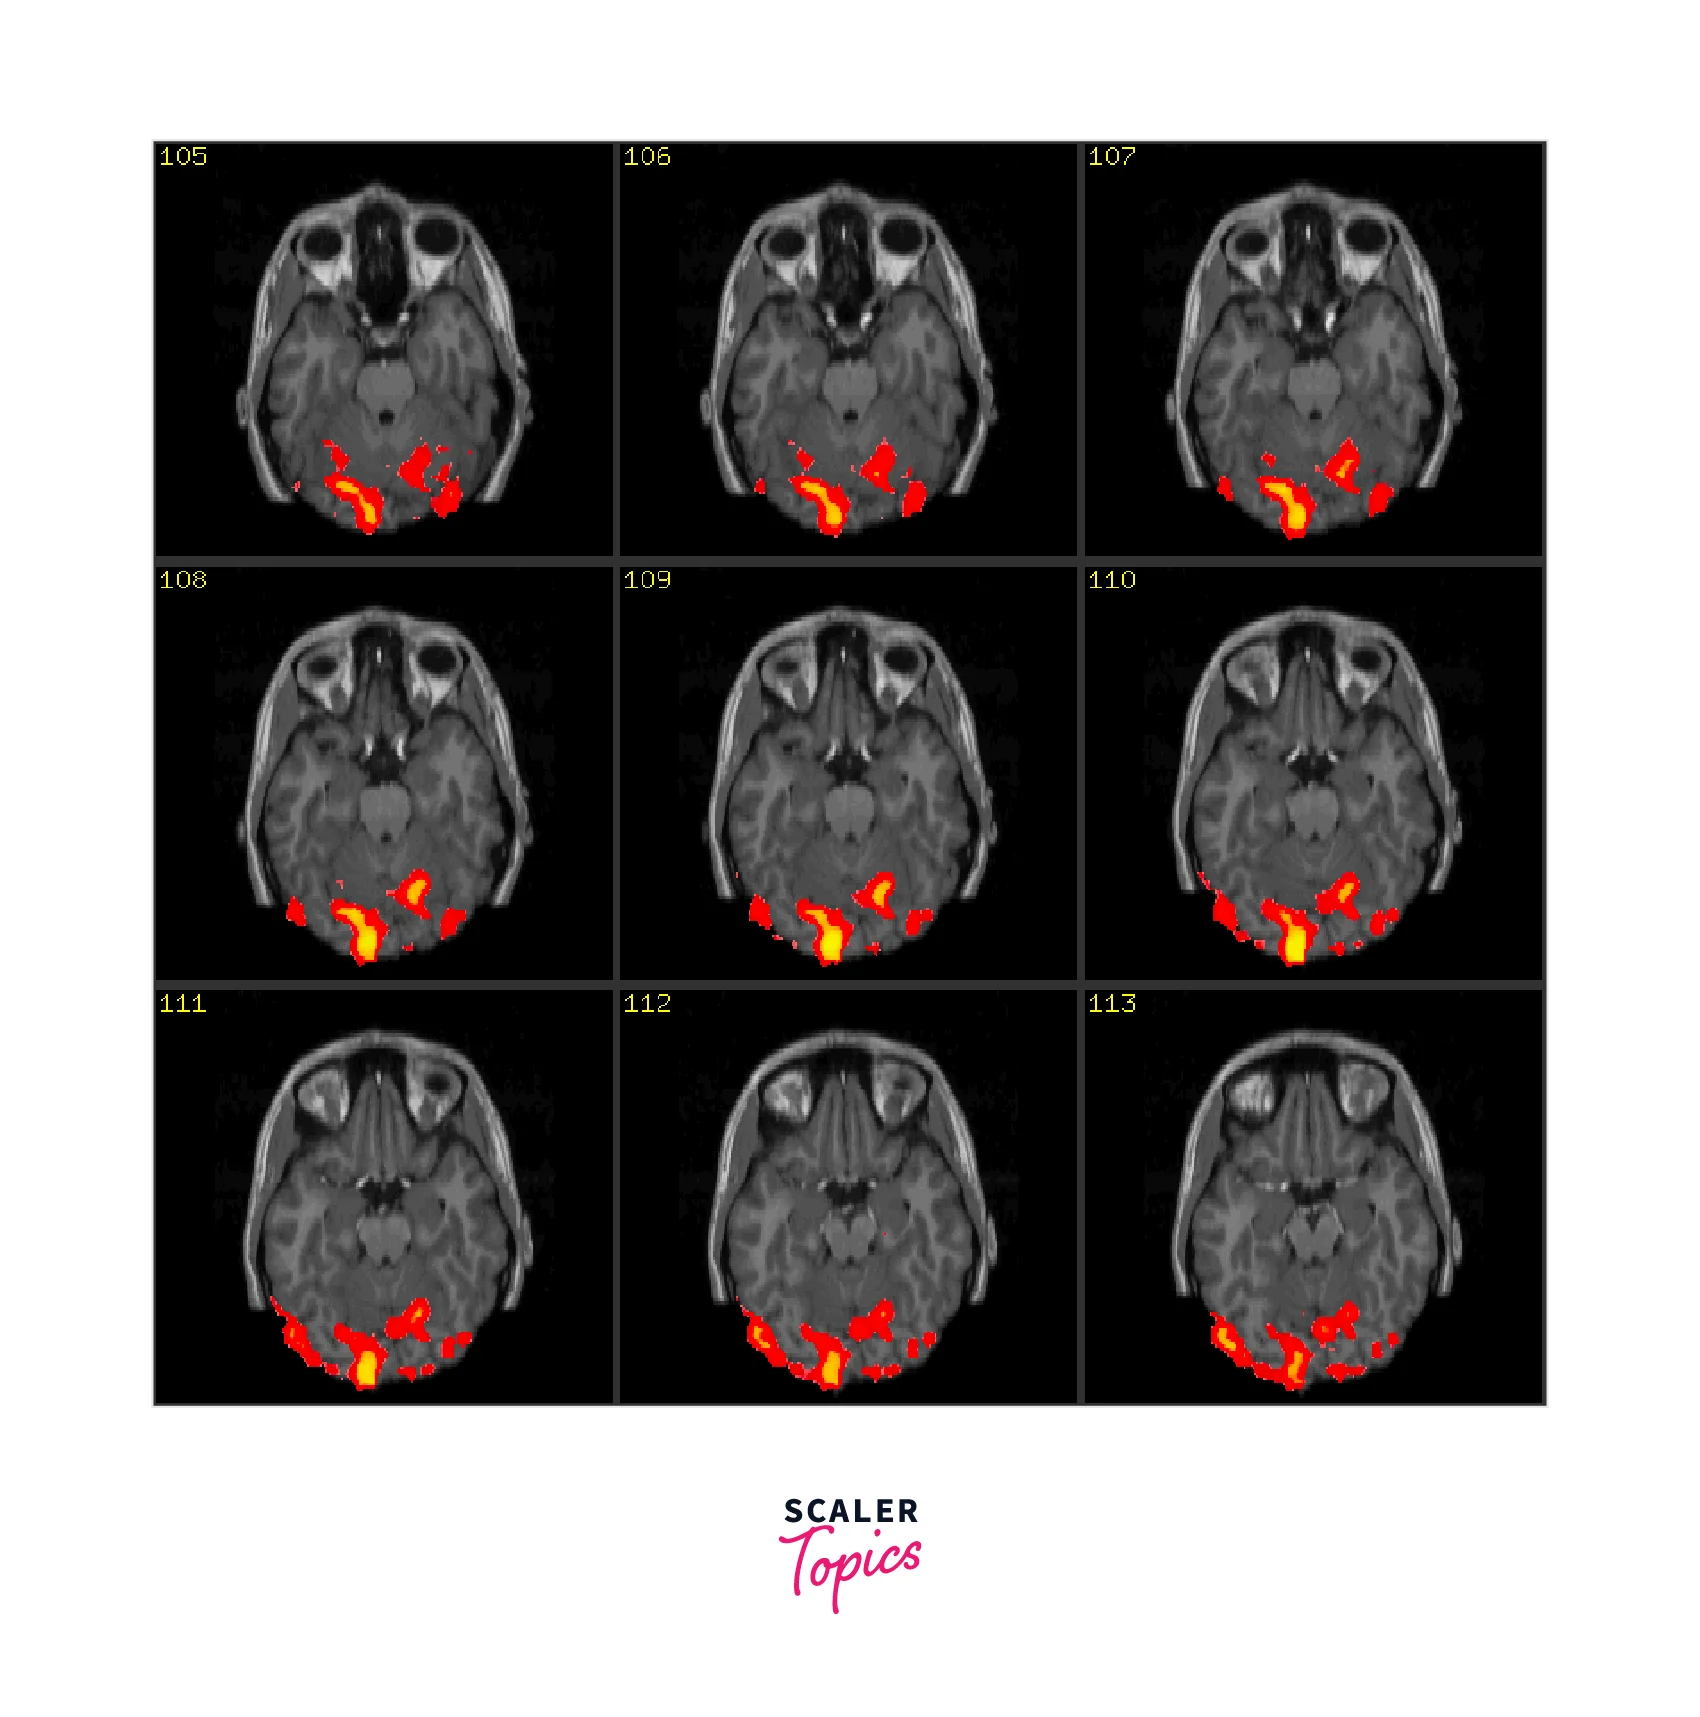

Neural Imaging:

AI can be used to analyze data from functional magnetic resonance imaging (fMRI) scans, which measure blood flow in the brain and provide information about neural activity. AI algorithms can be used to identify patterns and correlations between different brain regions and cognitive processes, allowing researchers to better understand the neural mechanisms underlying cognitive processes.